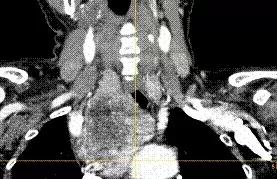

△CT影像可见甲状腺右叶下极显著增大,肿瘤延伸至胸廓入口下、向下延伸进入后纵膈,气管、食管受压左移